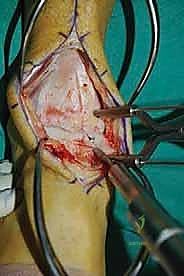

ثالثاً: الحل الجذري - إعادة بناء الطعم الخيفي الهيكلي

بالنسبة للمرضى الذين يعانون من آلام مزمنة، وتظهر صورهم آفة كبيرة الحجم، عميقة، تحتوي على تكيسات ضخمة، أو تشمل حواف التالوس (الكتف)، تصبح إعادة بناء الطعم الخيفي الهيكلي هي الحل الأمثل والذهبي.

الغوص العميق في جراحة الطعم الخيفي الهيكلي (Structural Allograft Reconstruction)

يهدف هذا الإجراء العبقري إلى استبدال الغضروف والعظم التالفين والميتين بنسيج سليم تماماً مأخوذ من متبرع متوفى (طعم خيفي - Allograft). هذا الطعم يتم تعقيمه وحفظه في بنوك الأنسجة العالمية وفقاً لأعلى المعايير الطبية الصارمة لضمان خلوه من أي أمراض معدية والحفاظ على حيوية الخلايا الغضروفية.

- الترميم التشريحي الحقيقي: يسمح باستعادة الشكل الهندسي الدقيق لعظم الكاحل، بما في ذلك المنحنيات المعقدة لكتف التالوس.

- توفير غضروف طبيعي (Hyaline Cartilage): الغضروف المزروع هو غضروف زجاجي طبيعي،